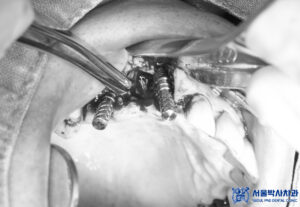

이후 발치 후 상악동거상술과

뼈이식을 동반한

무절개임플란트 수술을

진행하였습니다.

위, 아래 총 9개의

임플란트 식립이

이루어졌습니다.

<무절개임플란트>

컴퓨터 분석을 통해

미리 계산된 경로를 활용하여

임플란트 식립 오차가 줄어들며,

수슬 가이드를 활용하여

침습 범위가 매우 적습니다.

위의 사진과 같이

수술 가이드처럼 유도장치를

착영하고 수술을 진행하며,

위 장치는 고성능 3D 프린터로

컴퓨터 분석으로 정밀한

계산을 통해 제작됩니다.

이에 따라, 무절개임플란트는

임플란트 식립 위치가 정밀하며,

식립각도 오차가 줄어듭니다.